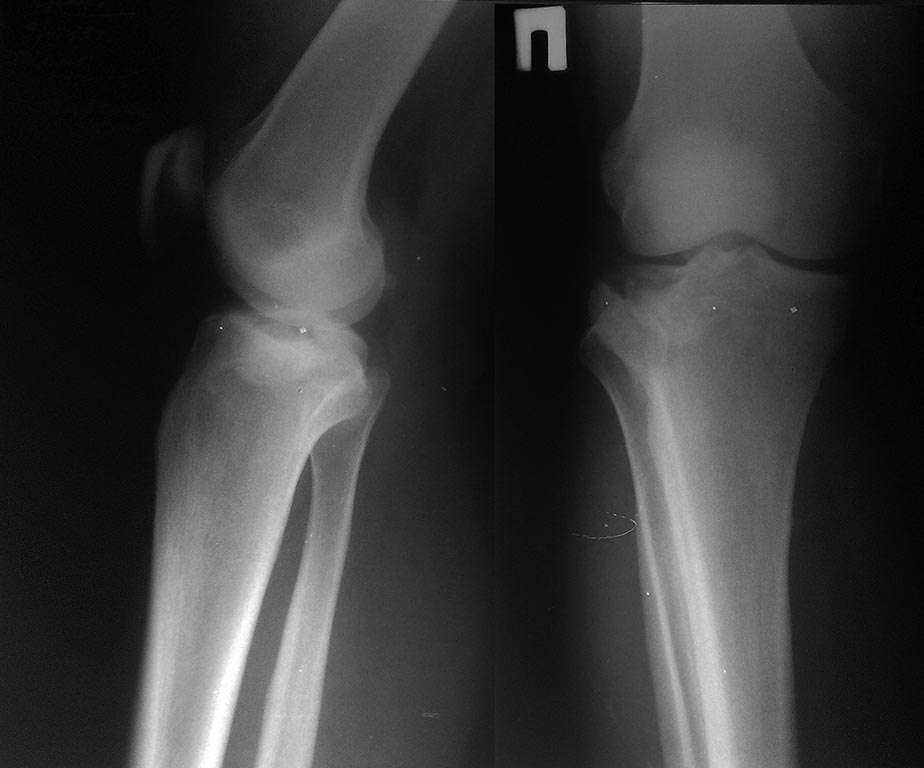

Больной 39 лет, травма от 09.11.13 г. в результате прямого удара по

голени бампером автомобиля. Наложена лонгета. В данный момент испытываю

трудности с тактикой лечения: консервативно или оперативно. Какие есть